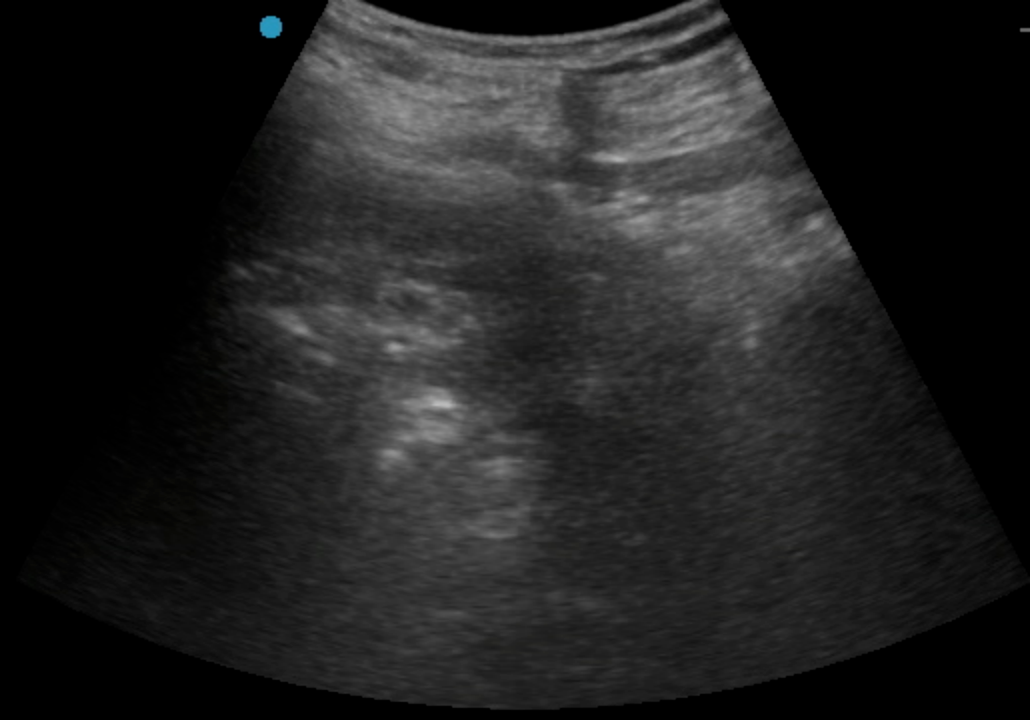

按照许主任本人通俗的说法,这是典型的手术指征明确、但病人基础条件恶劣的病例。对于麻醉提出了极大的挑战;由于患者透析以及下肢血栓抗凝的需要,下肢手术常用的椎管内麻醉出血风险太大,无法进行。而采用全身麻醉,患者肾衰以及心脑血管风险又会给围术期管理带来极大挑战。通过术前详细的评估,许主任最终决定对该患者实施单纯神经阻滞麻醉。考虑到抗凝带来的出血风险,优化了神经阻滞入路,采用了对凝血功能要求相对低的超声引导下前路腰丛+骶旁坐骨神经联合阻滞,精准覆盖术区,患者在清醒但完全无痛的状态下顺利完成手术,术后直接转回普通病房。同时,神经阻滞镇痛效果会持续十余个小时,也解决了术后镇痛问题。